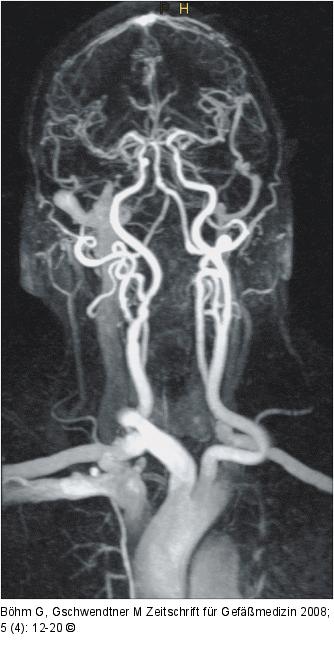

Abbildung 6: Arteria carotis

CE MRA gesamter Karotisverlauf